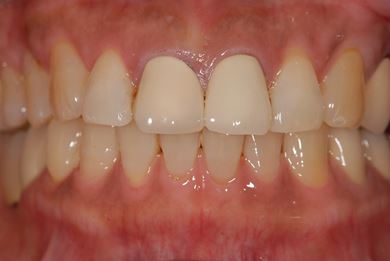

骨再生インプラント治療+セラミック治療+歯肉歯槽骨整形手術

| 治療内容 | インプラント2本(ソケットリフト、GBR)、メタルボンドセラミッククラウン3本、歯肉歯槽骨整形手術 | ||||||||||||||||||||||||||||||||

| 総治療費 | 1,315,650円 | ||||||||||||||||||||||||||||||||

| 治療期間 | 9ヶ月 |